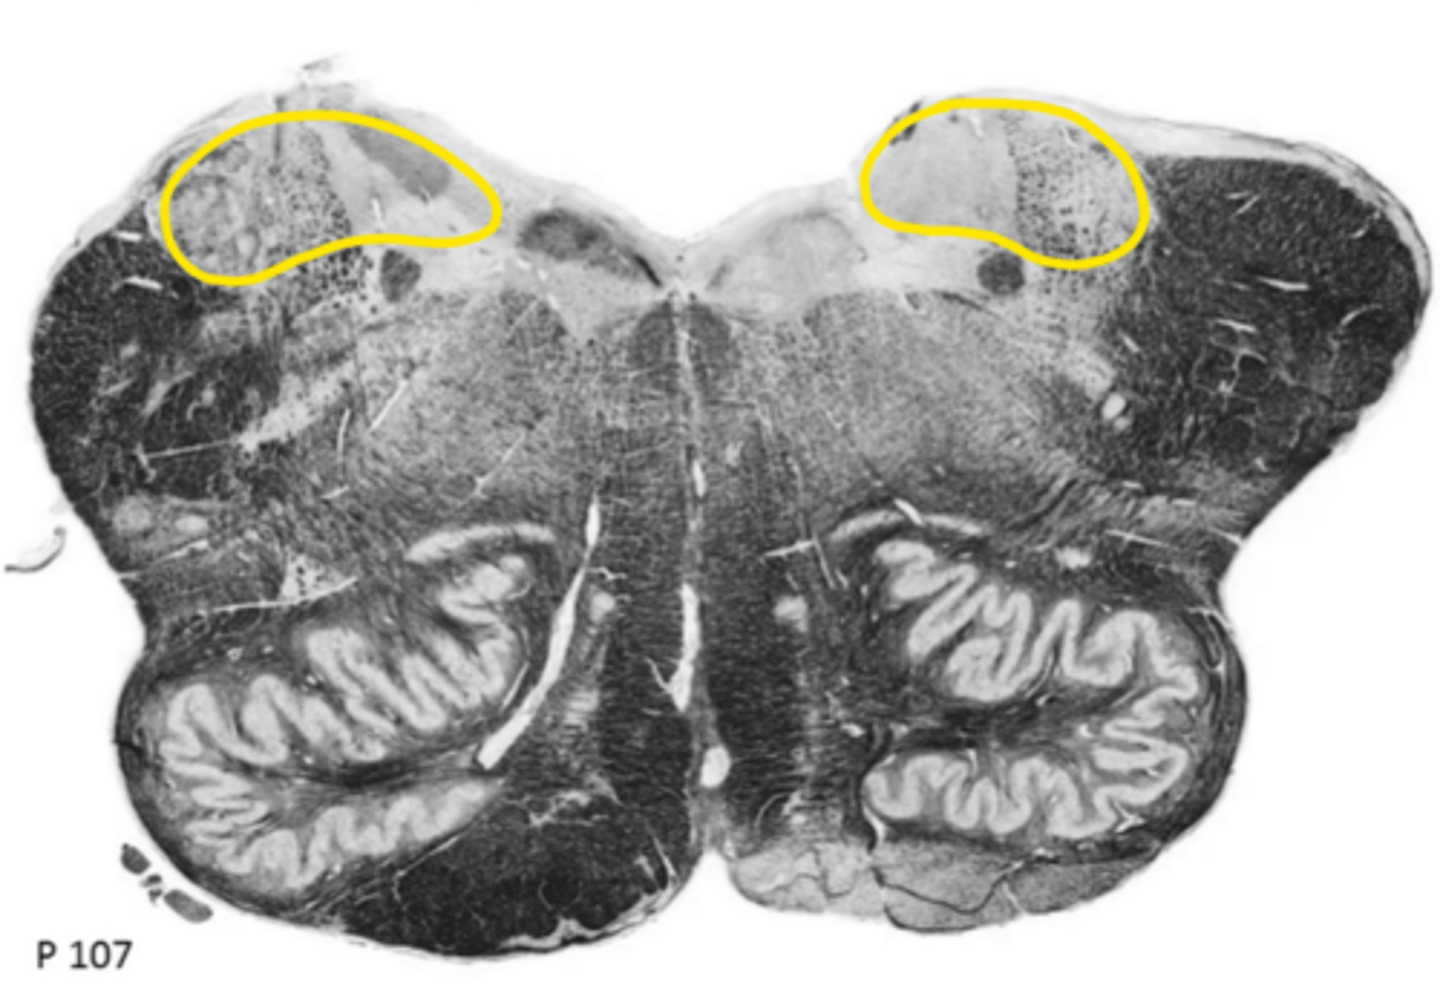

vestibular nucleus

ID the nucleus

cochlear nucleus